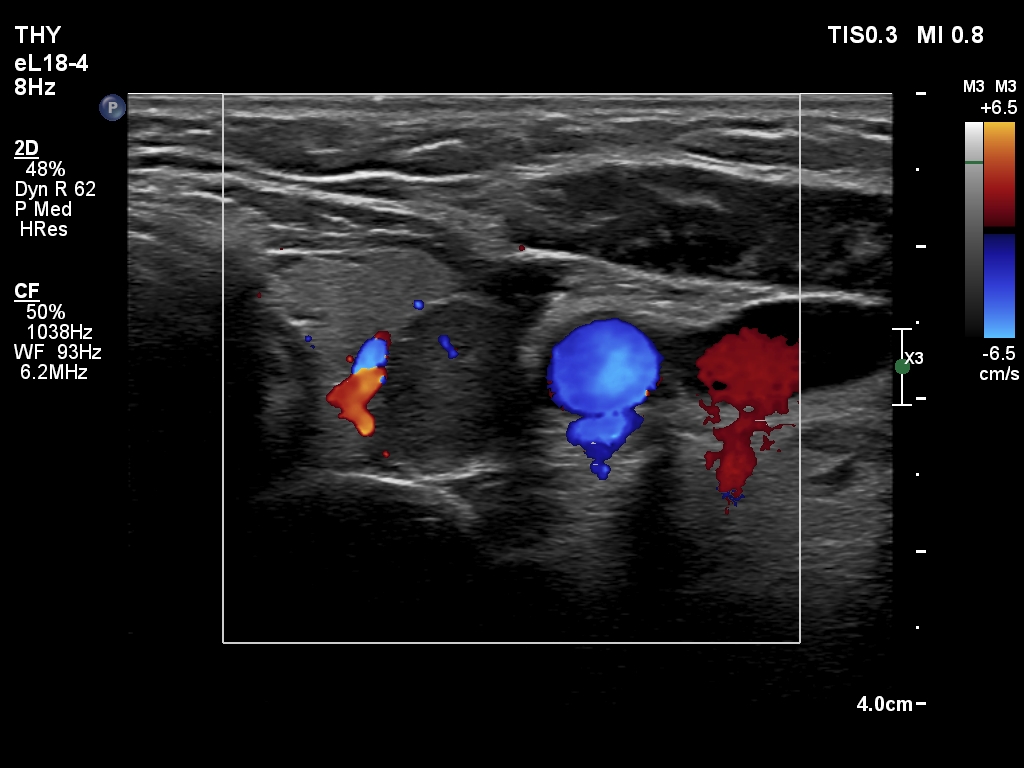

Right lobe, longitudinal scan

Middle part of the left lobe, transverse scan, color Doppler mode. The vascularization is scanty.